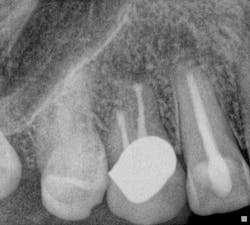

Fig. 6: Surgical preop radiograph. Endodontic treatment was necessary due to the presence of periapical pathology and acute symptoms, despite the radiographic appearance of the existing endodontic treatment being technically satisfactory. The presence of a long post, which is possibly serrated in nature and potentially actively engaging the root structure, is likely to compromise the potential for post removal and increase the risk of root fracture initiation, which would jeopardize the long-term survival of the tooth.

Fig. 7: Surgical postop radiograph. Surgical endodontic treatment was performed and the apical 3 mm to 4 mm of the root was reprepared using ultrasonics and sealed with MTA. A bone graft and resorbable membrane were placed to maximize the potential for osseous and soft tissue healing, especially with the proximity of the maxillary sinus to the surgical site. Case 2